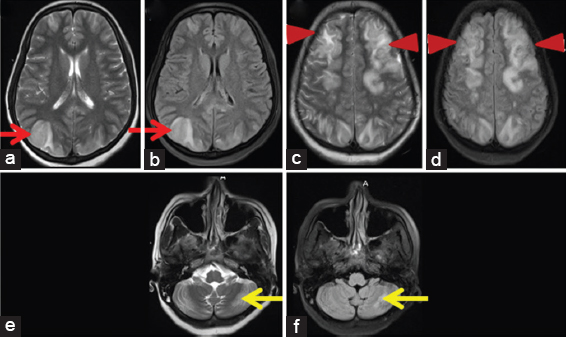

The patient developed post-procedure new episodes of seizures. The magnetic resonance imaging (MRI) brain was conducted on the 2nd day and was suggestive of bilateral symmetric T2 and FLAIR hyperintense signal in parieto-occipital and bilateral frontal (predominantly watershed) and bilateral cerebellum, leading to a possibility of posterior reversible encephalopathy syndrome (PRES) [Figure 1]. In view of abdominal pain with central nervous system involvement, urine sample was sent for urine PBG and aminolevulinic acid (ALA), and the patient was started on high dose glucose (300 g) per day (as an initial treatment plan as we suspected AIP). Meanwhile, patient's tachypnea worsen and she was kept on non-invasive ventilation. She had episodes of night terrors and hallucinations during the course. Urine PBG and ALA levels were high. The patient was started on 4 g/kg hematin. The abdominal pain was reduced significantly in next 2 days, but the patient had persistent behavior changes, hyponatremia, and blood pressure fluctuations. She had spontaneous abortion on the 4th day post-admission followed by a cardiac arrest and could not be revived after the event.